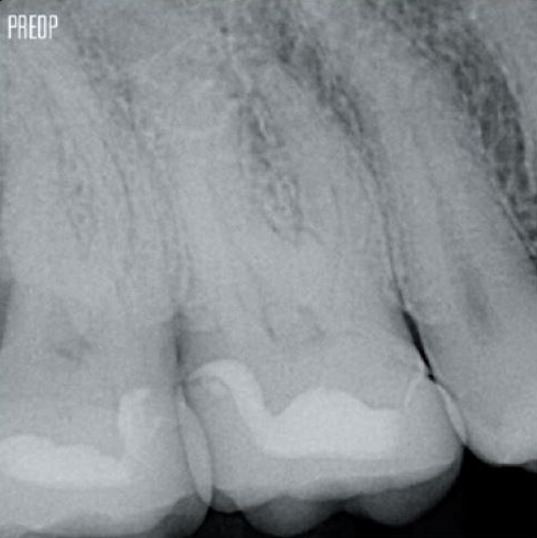

Fotos cortesía del Dr. Ahmed Salman

Un tratamiento exitoso de conducto radicular comienza con un acceso adecuado a la cámara pulpar. El procedimiento ideal proporciona acceso a la entrada del conducto radicular con una pérdida mínima de dentina.

Se recomienda utilizar una cavidad endodóntica conservadora (Conservative Endodontic Cavity, CEC) con el sistema TruNatomy®.

Ahora el acceso es posible desde diferentes ángulos mientras que, anteriormente, había que sacrificar la estructura (cavidad endodóntica tradicional).1

No es necesario el acceso en línea recta.1